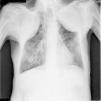

We report the case of an 87-year-old man, with a history of pulmonary tuberculosis in his youth, treated at the time with bilateral collapse therapy with oil (oleothorax).1 Over the years, this produced restrictive ventilatory changes with hypercapnic respiratory failure. He was hospitalized several times until he started nocturnal non-invasive ventilation.2 The patient continues to be monitored in our clinics. Therapeutic compliance is good and decompensations are rare.

Surgical procedures for the treatment of tuberculous lesions are divided into those intervening directly on the pulmonary lesions (exeresis or cavernostomy), and methods which induce the collapse of the cavities in the apex of the lung. Collapse procedures include thoracoplasty, which consists of narrowing the chest wall with the resection of several rib segments, paralysis of the diaphragm, and the introduction of air (pneumothorax) or oil (oleothorax) in the pleural cavity or the extrapleural space.

Surgical intervention in tuberculosis had its heyday between the end of the 19th century and the middle of the 20th, but was ultimately sidelined by the development of antituberculous drugs and combinations (Fig. 1).